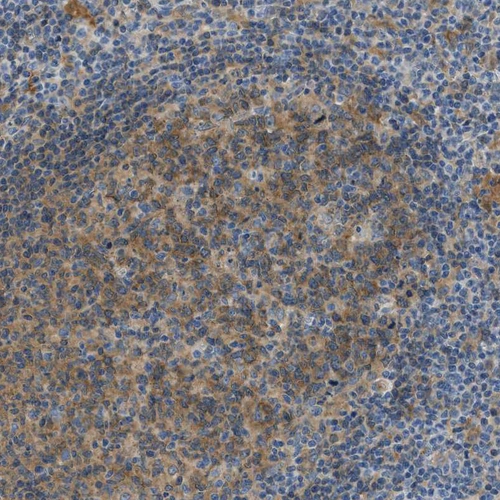

Immunohistochemical staining of human urinary bladder shows moderate to strong cytoplasmic / membranous positivity in urothelial cells.